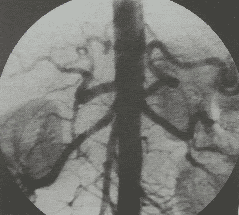

Trong khi đó, hệ thống chụp mạch máu số hóa xóa nền (DSA – viết tắt bởi cụm từ ” Digital Subtraction Angiography”) là phương pháp một chẩn đoán hình ảnh. Kỹ thuật chụp mạch máu số hóa xóa nền kết hợp giữa chụp X-quang và xử lý hình ảnh số, giúp chụp hệ thống mạch máu trong cơ thể và can thiệp điều trị. Ưu điểm nổi bật của phương pháp này là tính xâm lấn tối thiểu, không cần phải phẫu thuật mở.

Chụp số hóa xóa nền giúp chẩn đoán hình ảnh chính xác